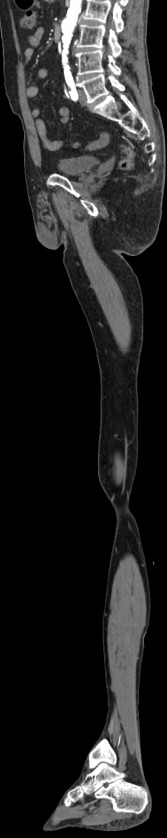

Мультиспиральная компьютерная томография является современным методом обследования сосудистой системы нижних конечностей. Такое исследование по-другому называется КТ-ангиография. Методика позволяет с помощью рентгеновского излучения получить посрезовые снимки и после цифровой обработки создать объемные модели кровеносной системы обеих ног.

В наших медицинских центрах КТ-ангиография нижних конечностей выполняется на современных мультиспиральных компьютерных томографах экспертного уровня TOSHIBA AQUILION. Аппараты послойно сканируют область исследования, одномоментно выполняя множество тончайших срезов. В результате получаются снимки высокого качества и трехмерные модели с изображением даже мелкой сосудистой сети нижних конечностей. При этом методика скоростного мультисрезового сканирования обеспечивает минимальную дозу рентгеновского облучения для пациента.

• КТ сосудов от бифуркации аорты до коленного сустава (оценивается нижняя часть брюшной аорты, разветвление аорты, подвздошные артерии, бедренные и подколенные артерии)

• КТ сосудов от бифуркации аорты до стопы (данный протокол обследования включает в себя полное обследование сосудов нижних конечностей, включая стопы)